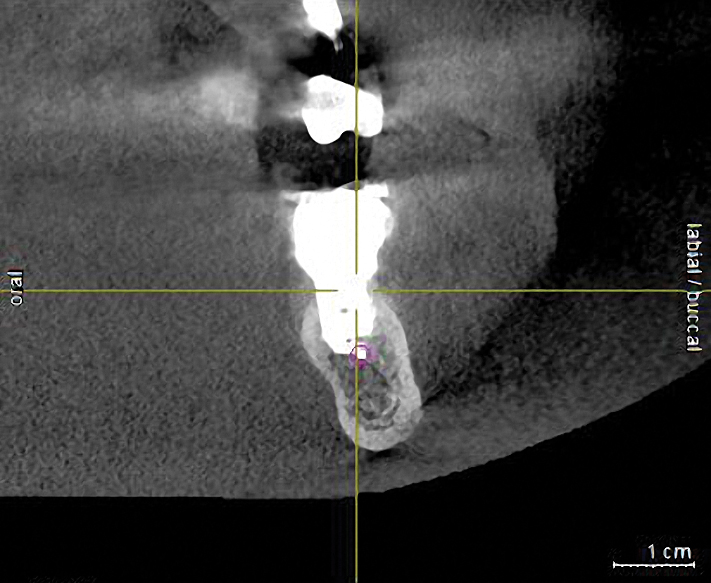

To ensure correct implant placement with the least amount of complications, preoperative planning is necessary. Avoiding nerve injuries starts with proper patient selection, which is done in association with good diagnostics. If it is believed that a computerized tomography (CT) scan or surgical guide would be beneficial, then it should be utilized. Individuals performing surgeries must confirm the path of the mandibular nerve that may have been outlined on a scan by a radiologist. When placing dental implants, a 2-mm safety zone should be left apical to implants over the IAN to accommodate minor drilling errors and drill lengths should be adjusted to take into account radiographic distortion.19,29 In addition, the 2-mm safety zone may help avoid pressure placed on the nerve due to bone compression when the implant is placed close to the mandibular or mental canals (Figure 1 and Figure 2). If necessary, short implants can be used to remain in the safety zone.30 Clinicians should also be aware that drill markings to denote bur length do not take into consideration the extra length of the tapered drill tip, which can add anywhere from 0.4 mm to 1.5 mm to the actual drill size.19,31 In addition, over the IAN or mental nerve, it is advantageous to use drill stops to avoid over-drilling.19,31 It should be underscored that the thickness or density of the bone surrounding the IAN does not provide substantial resistance to drill penetration and excess force should be avoided when drilling over the IAN.32

Subsequent to nerve injury, the clinician needs to determine if immediate referral is necessary or a pharmacologic approach is warranted or if implant removal or reverse-torquing it a little would best serve a patient. There are diverse opinions in the literature pertaining to when and under what conditions referral to a microsurgeon is needed.58,59 It is generally agreed that if a clinician believes that a nerve has been transected as a result of an implant procedure, immediate referral is warranted.12,51,54,60,61 On the other hand, if a patient manifests neurologic symptoms post-implantation, but the clinician is sure that the drill never entered the mandibular canal, it is possible that postoperative altered sensation is caused by traction of a nerve or an inflammatory process. Then a pharmacologic approach may be warranted.3 A clinician can be almost sure that the drill did not enter the mandibular or mental canal if after each drill, the floor of the osteotomy was checked with an implant probe or if a radiograph clearly depicts the osteotomy terminated several millimeters from the nerve canal. The previous remark is qualified, because there is the remote possibility that some unusual branch of the IAN was present and damaged. From another perspective, a CBCT scan can be ordered to attain an enhanced view of the implant’s relationship to vital structures if a 2-dimensional radiograph was initially used to assess the situation (Figure 1 and Figure 2).

Fig 2. The implant restoration was completed 10 years ago and the patient has been able to accommodate the altered nerve sensation. Recently, the patient presented at one of the authors’ offices and a CBCT scan was ordered. It demonstrated that the implant at site No. 30 is closer to the inferior alveolar canal than previously envisioned and may be causing compression on the nerve.

Figure 2